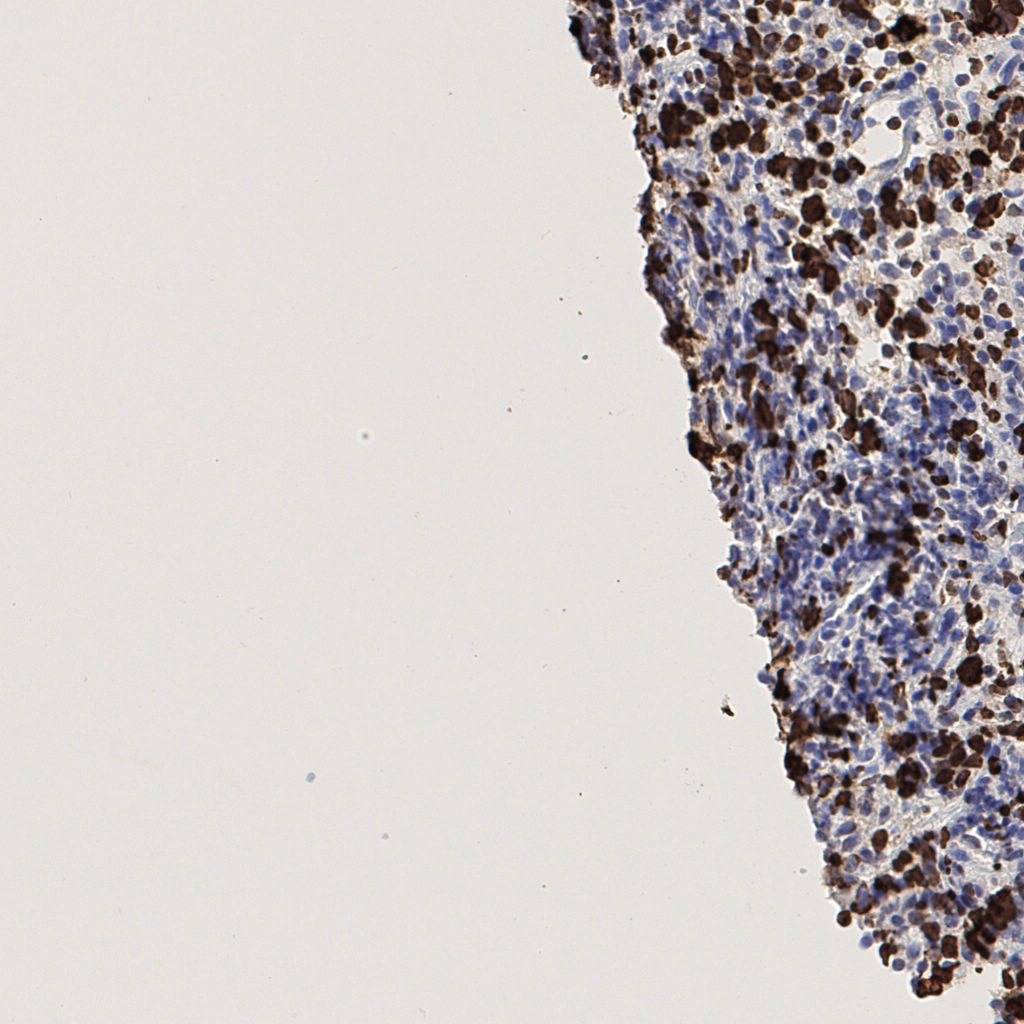

7.85%

Ki67 指数

阴 1104 阳 94

H255858-KI-67.ndpi